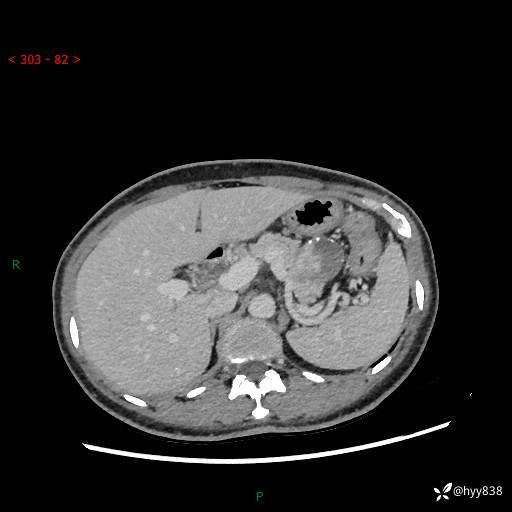

胰腺CT平扫

img